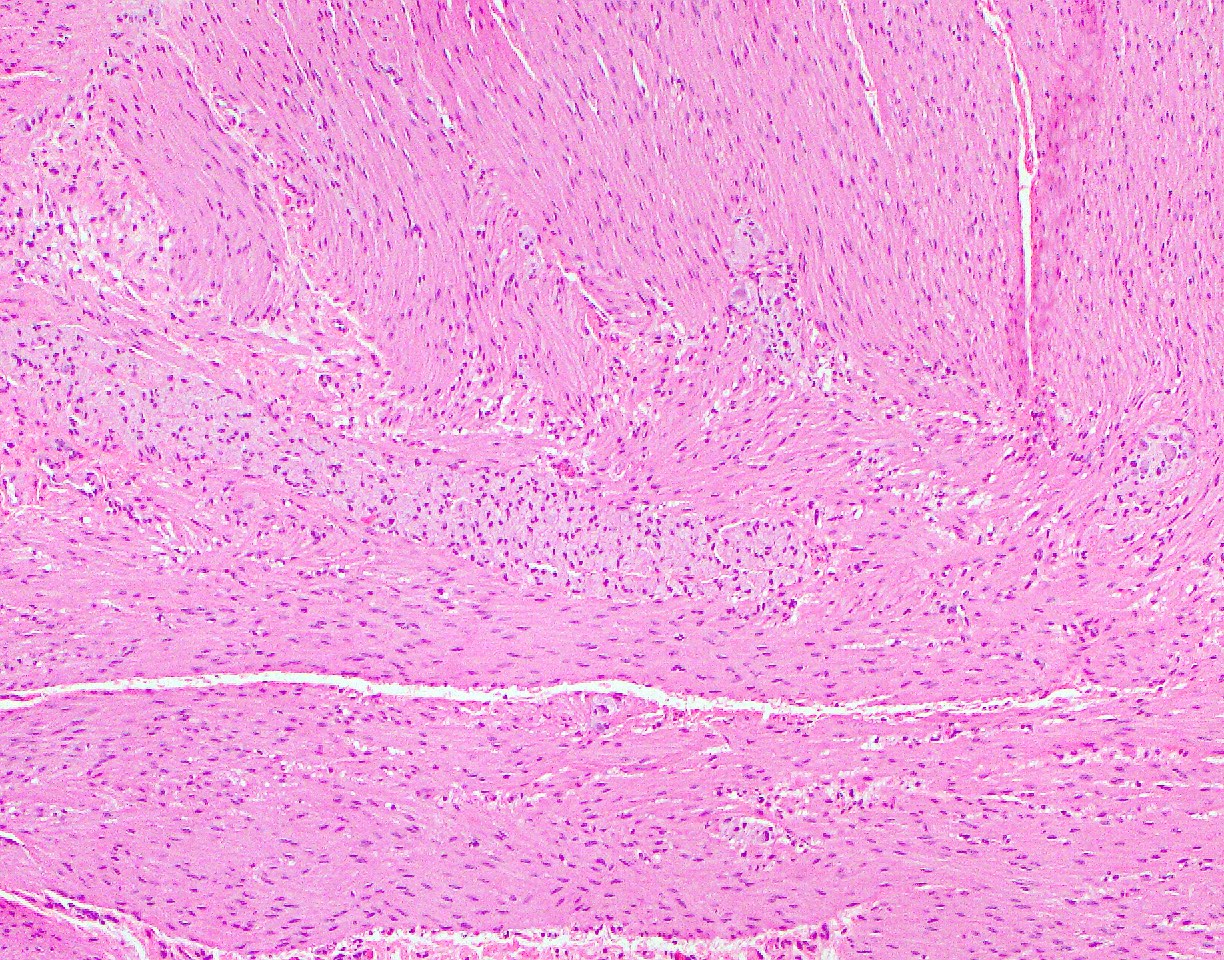

- Muscularis mucosa:

- Muscularis mucosa consists of thin strands of smooth muscle fibers separating the mucosa and submucosa

- Presence of muscularis mucosae in biopsies is critical to evaluate for architectural distortion

- Muscularis propria:

- Consists of inner circular layer and outer longitudinal layer and Auerbach nerve plexus in between the 2 muscle layers

- Interstitial cells of Cajal are present within the muscularis propria and play a role in peristalsis

- Subserosa and serosa: subserosa is composed of fibroadipose tissue and is covered by the serosa lined by cuboidal mesothelial cells

Microscopic (histologic) images